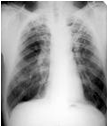

Tuberculosis

A infection of the lungs, Tuberculosis is caused by the bacteria "Mycobacterium tuberculosis". The germ enters the body through nose, mouth or windpipe and stays down in the tile lungs. The causes of tuberculosis include low resistance of the body, smoking, drinking and stress. The symptoms of this disease begin with cough and extend to chest pain, prolonged coughing and bringing out blood with cough. Fever, chills, sweating at night, loss of appetite and weight loss are some other symptoms associated with tuberculosis.